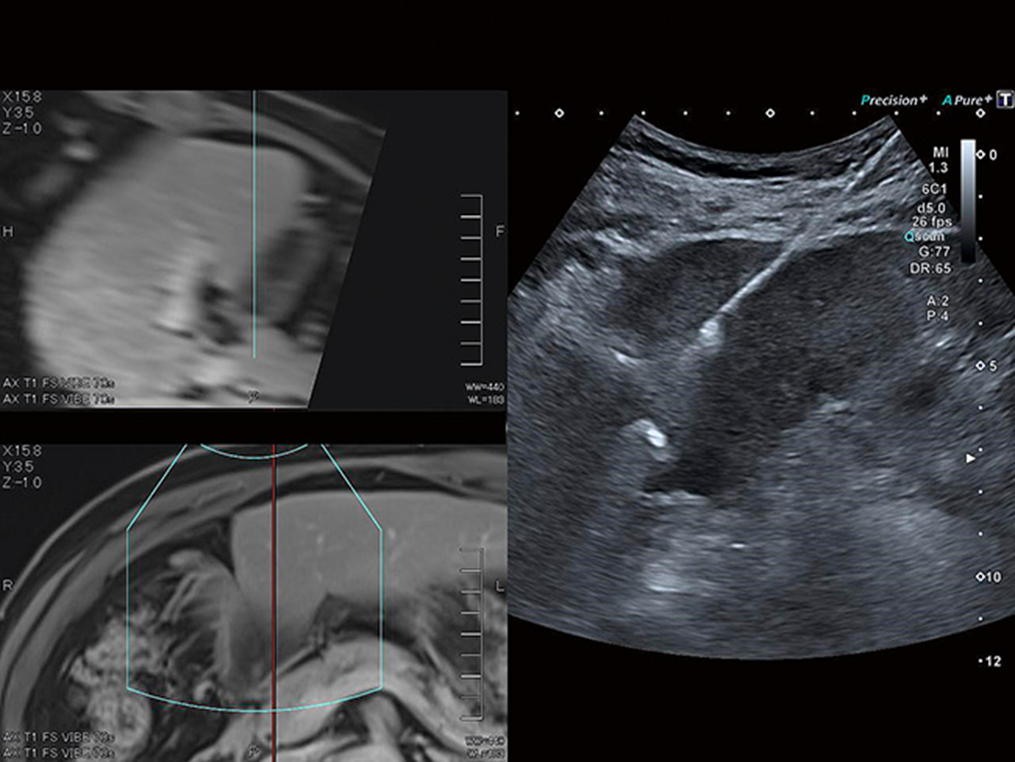

Smart Fusion hợp nhất siêu âm thời gian thực với dữ liệu CT, MR hoặc siêu âm đã thu được trước đó, cho phép bạn xác định và so sánh các tổn thương một cách dễ dàng và điều hướng giải phẫu phức tạp một cách tự tin.